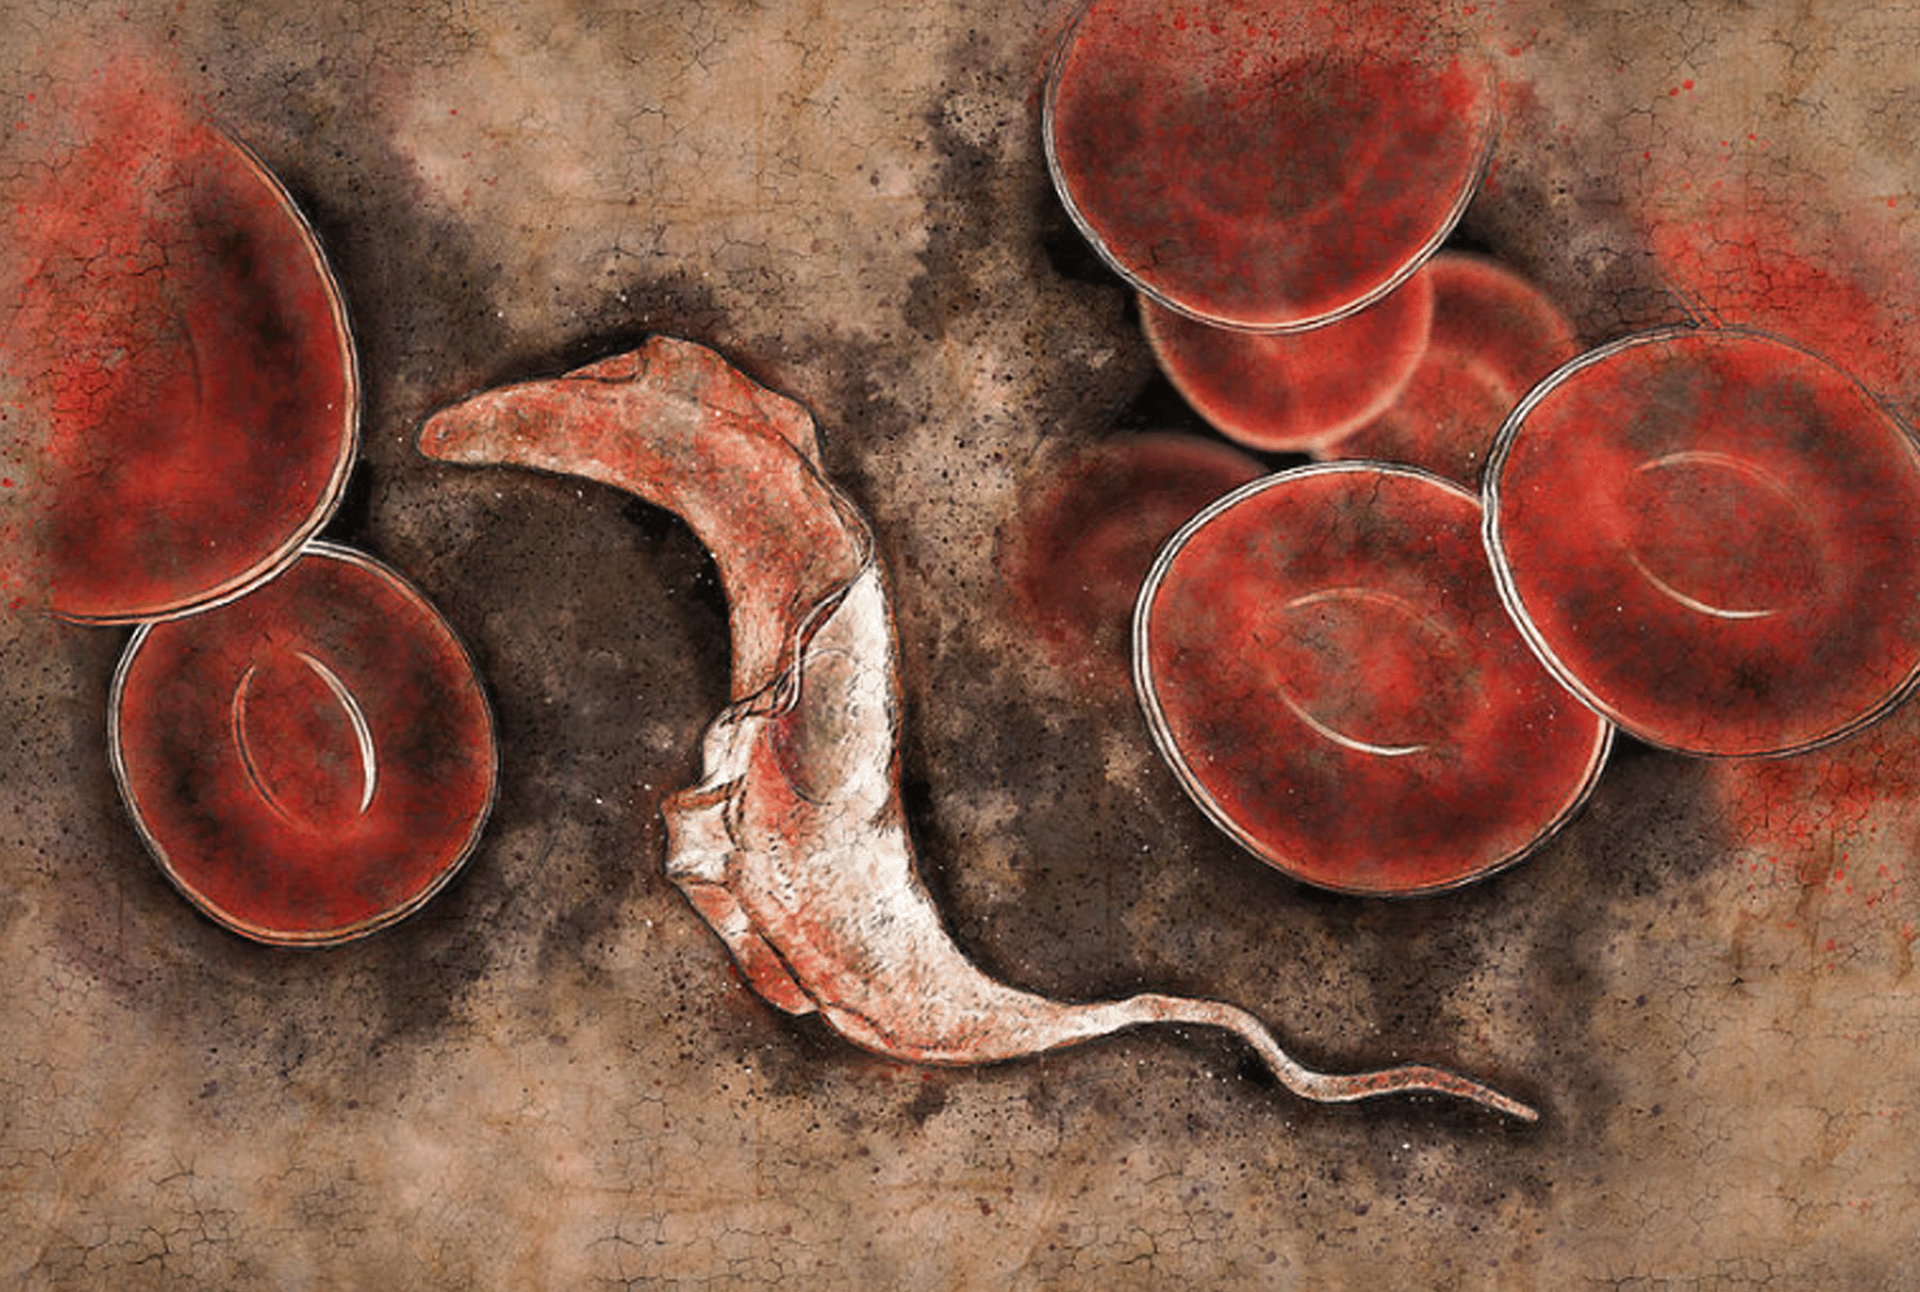

La lucha contra la enfermedad de Chagas:

Detección precoz y atención a lo largo de toda la vida

Entre seis y siete millones de personas infectadas en todo el mundo

Aproximadamente 12 000 muertes al año relacionadas con la enfermedad

Entre 30 000 y 40 000 casos nuevos cada año

En 2024 queremos llamar la atención sobre la enfermedad de Chagas y sobre el sufrimiento que causa, y exigir un acceso equitativo a la atención y los servicios de salud para todas las personas afectadas por la enfermedad.

El lema de este año es «La lucha contra la enfermedad de Chagas: Detección precoz y atención a lo largo de toda la vida», con el que se pretende aumentar la concienciación pública sobre la enfermedad de Chagas y atraer más fondos y apoyo para las iniciativas orientadas al diagnóstico precoz y la atención integral de seguimiento.

La enfermedad de Chagas es prevalente entre las poblaciones pobres de las regiones continentales de América Latina, pero cada vez se detecta con más frecuencia en otros países y continentes.

A menudo se la describe como una «enfermedad silenciosa y silenciada», ya que la mayoría de las personas infectadas no presentan síntomas o estos son extremadamente leves. En todo el mundo hay aproximadamente entre 6 y 7 millones de personas infectadas por la enfermedad de Chagas, y cada año causa la muerte de 10 000 personas.